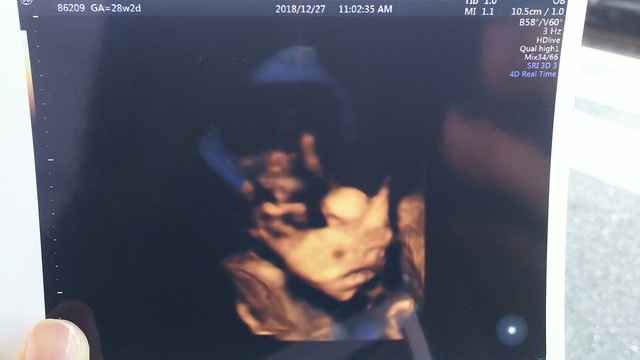

28週2日(28w2d)のエコー写真

28週2日(28w2d・男の子)かっぴー&コロ助 さん(33歳)

エコー写真撮影時のエピソード:

いつもエコーを撮る時、なかなか顔を見せてくれず、ほとんどが下半身ばかり(笑) でもこの時はドヤ顔を見せてくれて大笑いしました!

この頃は胎動も激しく毎日お腹をドカドカ蹴っ飛ばしてました!今でも脚の力は凄いです。 そんな息子も半年後にはお兄ちゃんに。